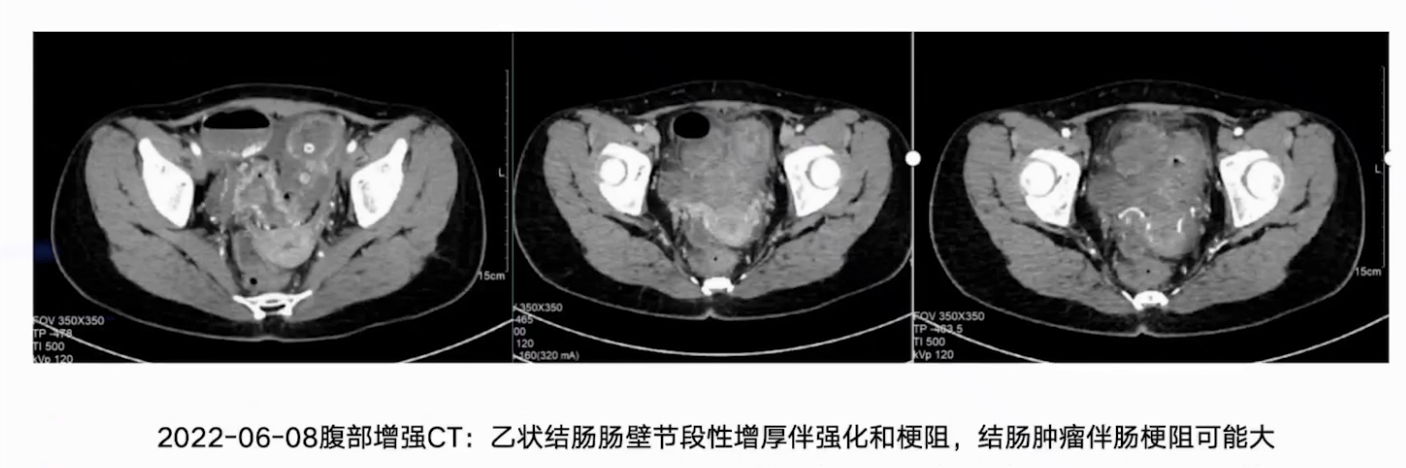

6月8日完善腹部增强CT和结肠镜检查,腹部增强CT提示乙状结肠肠壁截断性增厚伴强化和梗阻,结肠肿瘤伴肠梗阻可能性大。